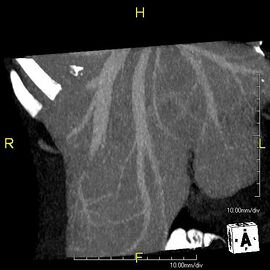

صورة مقطعية محورية تظهر أوردة كبدية شاذة تنتشر على السطح الأمامي تحت المحفظة للكبد.[73]